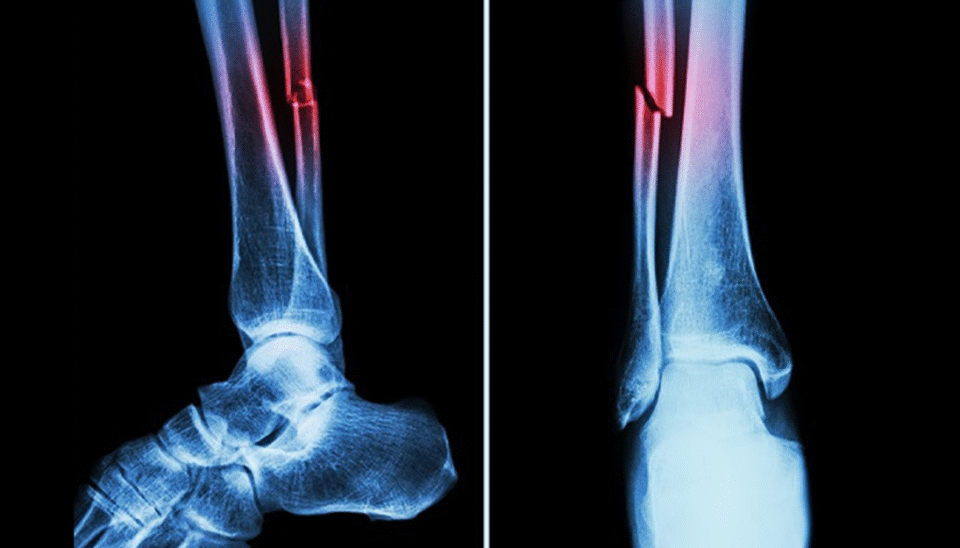

چین کے محققین نے ہڈیوں کے فریکچر کو منٹوں میں جوڑنے والا انقلابی سپر گلو تیار کر لیا ہے، جو روایتی طور پر کئی ماہ کے بعد جوڑنے والی ہڈیوں کے علاج کو چند منٹوں میں ممکن بنا دیتا ہے۔

چین کی ژے جیانگ یونیورسٹی کے ماہرین نے اس سپر گلو کو بون-2 کا نام دیا ہے، جو پہلے ہی 150 سے زائد کامیاب طبی تجربات میں استعمال ہو چکا ہے، ماہرین کے مطابق یہ چپکنے والا مادہ محض ایک انجکشن کی صورت میں ٹوٹے ہوئے ہڈی کے ٹکڑوں کو صرف تین منٹ میں جوڑ دیتا ہے۔

ہانگزو کے آرتھوپیڈک سرجن ڈاکٹر لن شیان فینگ کے مطابق عام حالات میں ہڈی کے فریکچر کو جوڑنے میں مہینوں لگتے ہیں اور اس دوران مریض کو دھات کی پلیٹس، آپریشن اور پیچ لگانے جیسے تکلیف دہ مراحل سے گزرنا پڑتا ہے، لیکن بون-2 نے اس عمل کو آسان اور تیز رفتار بنا دیا ہے۔